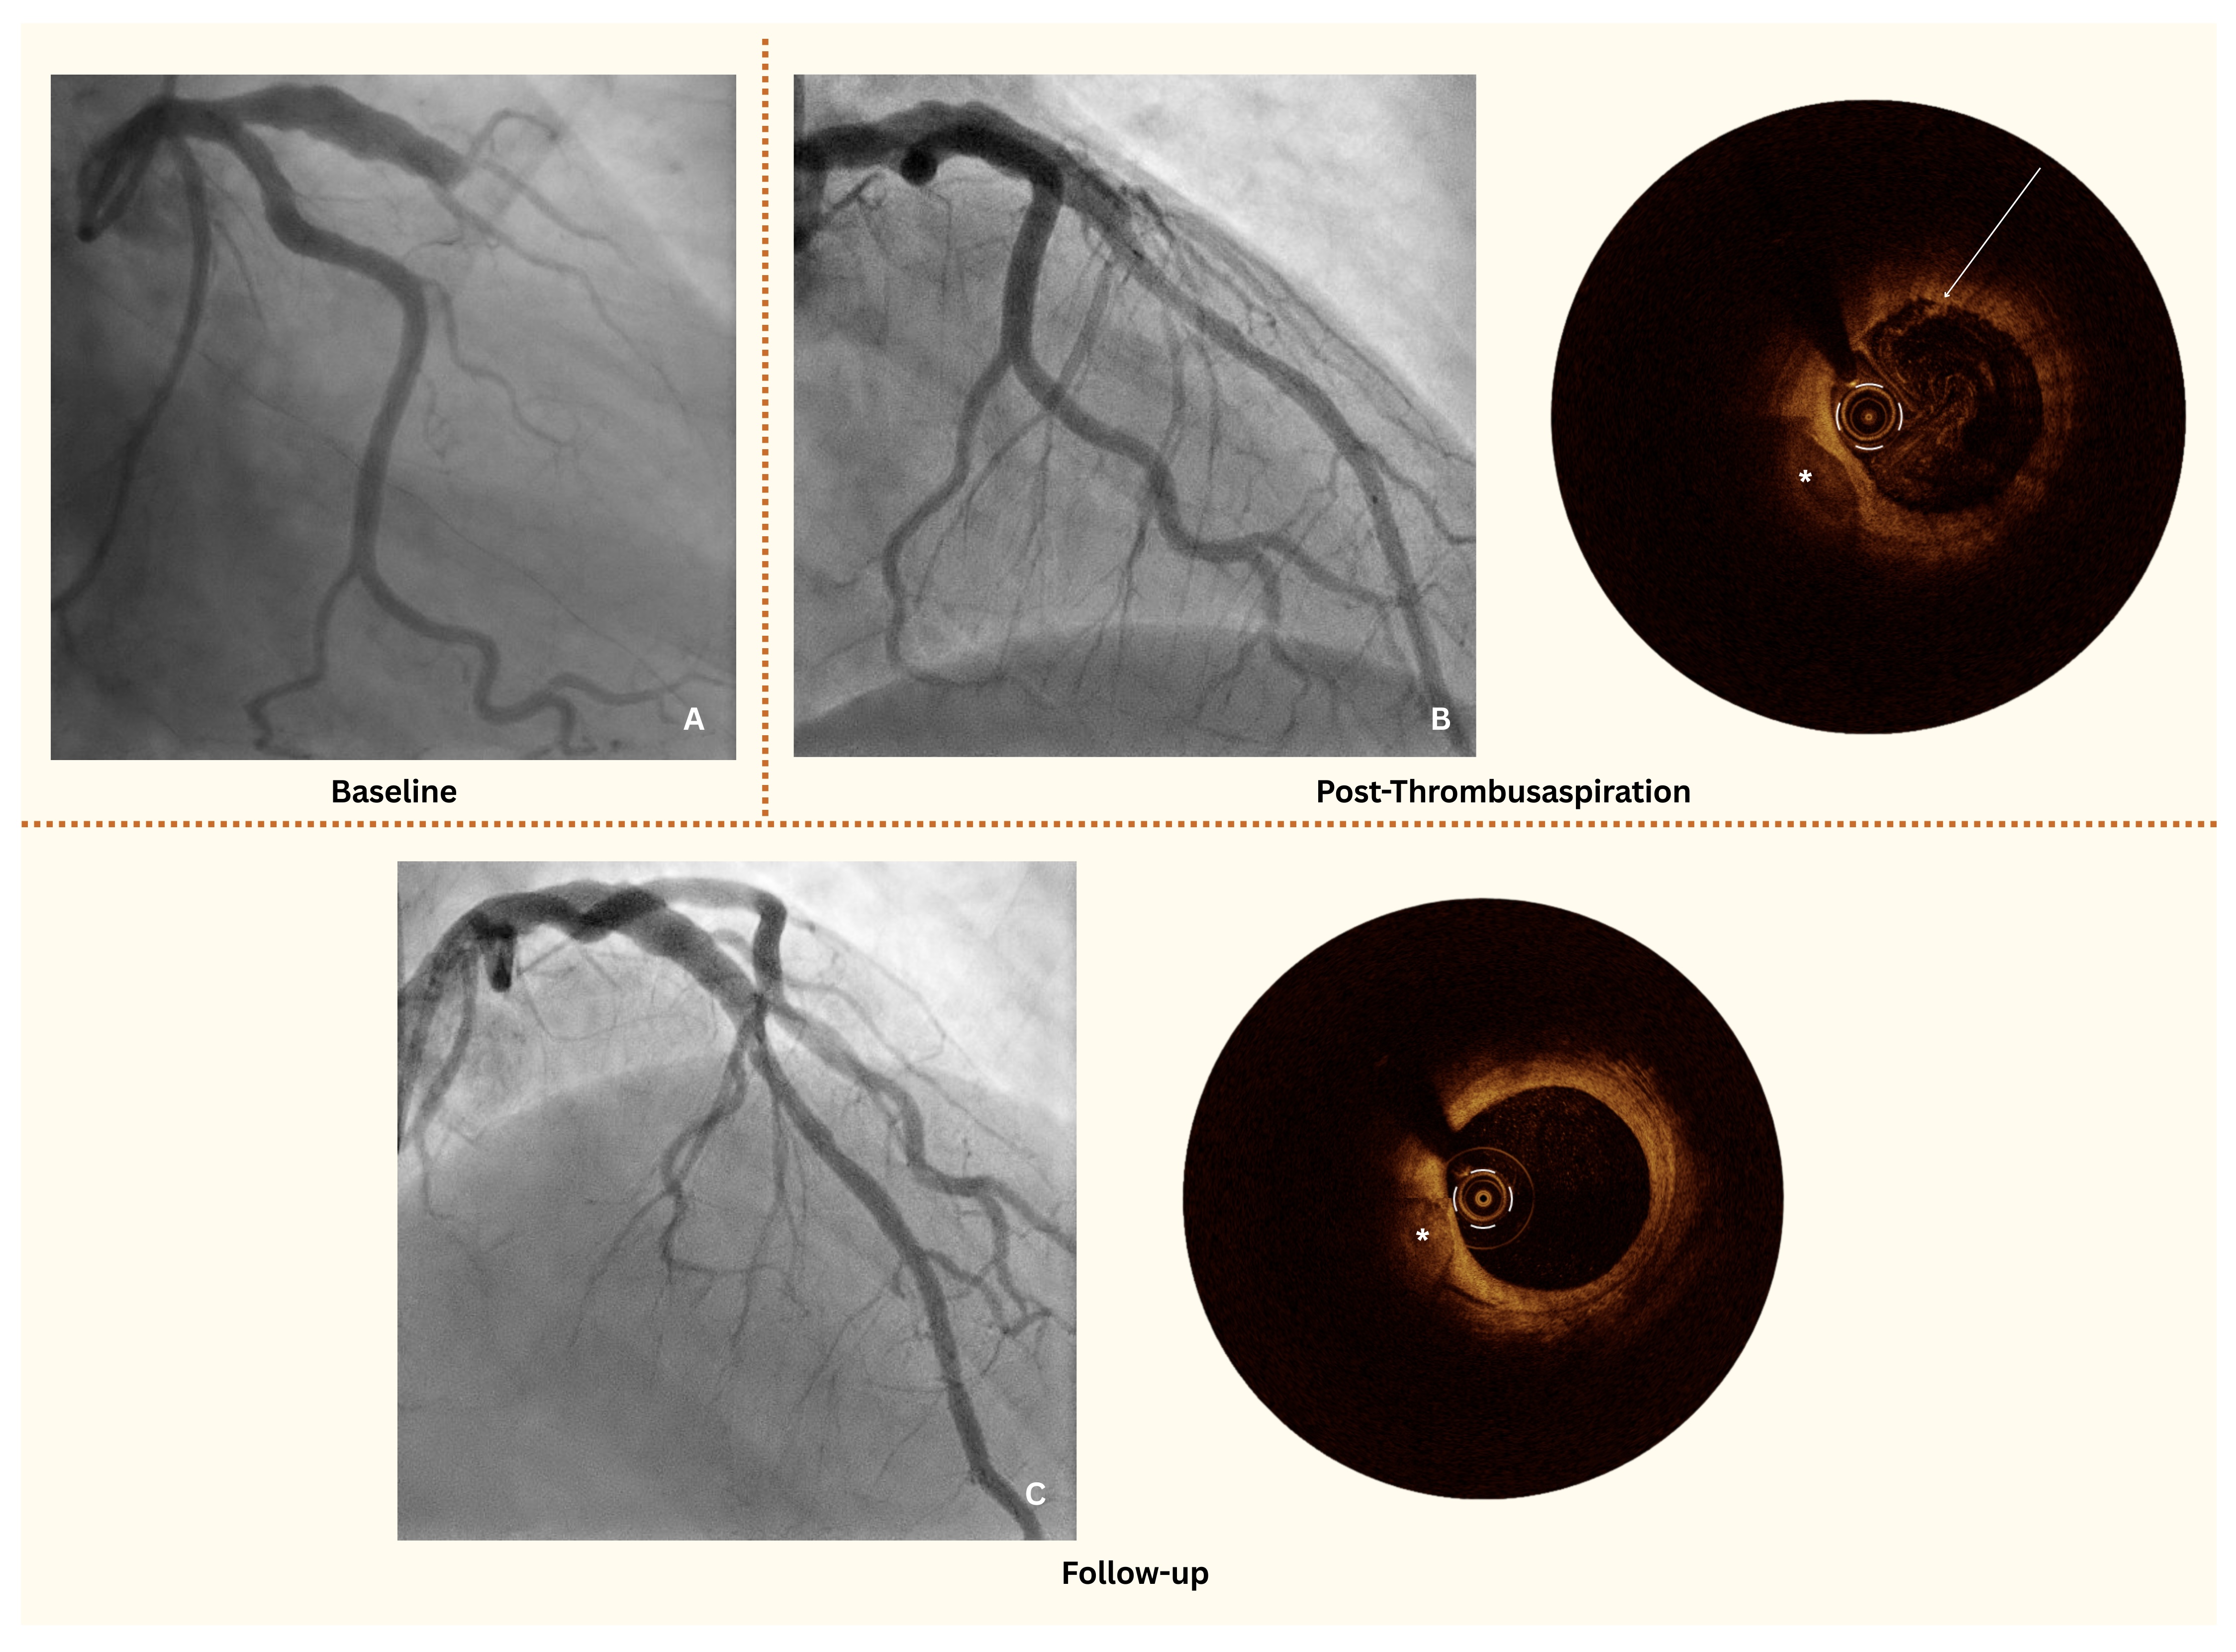

A 49-year-old man was transferred to our department by emergency medical services with an anterior ST-segment elevation myocardial infarction (STEMI). The patient reported left-sided thoracic pain radiating to the left arm, accompanied by autonomic symptoms with an onset approximately 8 hours prior to admission. The initial electrocardiogram (ECG) showed 2- to 3-mm ST-segment elevations in leads V3-V5. Coronary angiography revealed total thrombotic occlusion of the mid-left anterior descending artery (LAD), with notable adjacent coronary artery ectasia (CAE) (Figure A).

To further assess the culprit site, optical coherence tomography (OCT) was performed. While full circumferential imaging of the culprit site was achieved, assessment at the ectatic segment was limited because of the vessel's dilated morphology. OCT revealed a white thrombus overlying an intact fibrous cap, consistent with an acute coronary syndrome (ACS) with intact fibrous cap (IFC), ie, coronary plaque erosion (Figure B, Video 1). However, there was no evidence of a significant coronary stenosis or plaque rupture, leading to the decision against stent implantation.

The patient was treated with thrombus aspiration followed by intracoronary tirofiban with a 24-hour infusion and dual antiplatelet therapy (DAPT) with a planned duration of 12 months, and extended DAPT to be evaluated at follow-up. A follow-up coronary angiography with OCT at 6 weeks confirmed thrombus resolution and the absence of significant stenosis or pathological plaques in the LAD (Figure C, Video 2), supporting the effectiveness of the conservative approach.